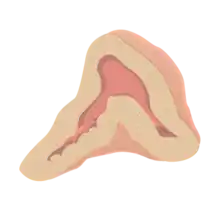

| Normal remnant adrenal gland (left) with a pheochromocytoma (right) involving the adrenal medulla | |